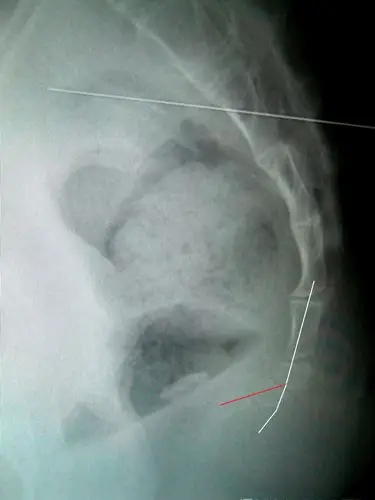

坐下时被拉开椅子摔在地上了,去医院拍了x光,说是尾5椎体向上明显移位

尾椎骨错位

骶尾部骨折